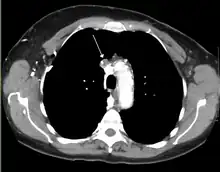

The main techniques of diagnosing SVCS are with chest X-rays (CXR), CT scans, transbronchial needle aspiration at bronchoscopy and mediastinoscopy.[6] CXRs often provide the ability to show mediastinal widening and may show the presenting primary cause of SVCS.[6] However, 16% of people with SVC syndrome have a normal chest X-ray. CT scans should be contrast enhanced and be taken on the neck, chest, lower abdomen, and pelvis.[6] They may also show the underlying cause and the extent to which the disease has progressed.[6]